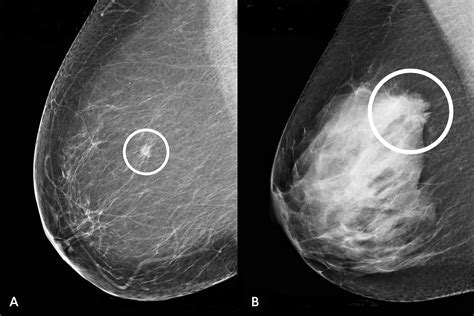

When a radiologist analyzes your scans, they are assessing the appearance of your breast tissue to ensure there are no signs of malignancy. Normal mammogram images typically display a balanced composition of fatty tissue, glandular tissue, and fibrous connective tissue. Because every woman’s breast density is unique, these images do not look identical for everyone; however, a "normal" result means the radiologist has not identified any suspicious masses, architectural distortions, or unusual clusters of microcalcifications that would necessitate further investigation.

Radiologists look for consistency and symmetry between the left and right breasts. While minor asymmetries are common, a significant change in the pattern of your tissue over time is what prompts a "call-back" for further testing. Essentially, normal results indicate that the internal anatomy of your breast appears healthy and consistent with your medical history and age-related tissue changes.

One of the most important factors influencing the appearance of your scan is breast density. Dense breast tissue contains more fibrous and glandular tissue compared to fatty tissue. On a mammogram, fatty tissue appears dark and transparent, while dense tissue appears white and opaque. This is why understanding density is vital when viewing normal mammogram images:

- Fatty Breasts: These are easier to read because masses stand out clearly against the dark background.

- Scattered Fibroglandular Densities: This is a very common classification where most of the tissue is fatty but with some scattered areas of density.

- Heterogeneously Dense: This tissue can make it harder to see small masses, as the white density can "mask" potential concerns.

- Extremely Dense: This classification presents the highest challenge for standard imaging, sometimes requiring additional screening like ultrasound or MRI.